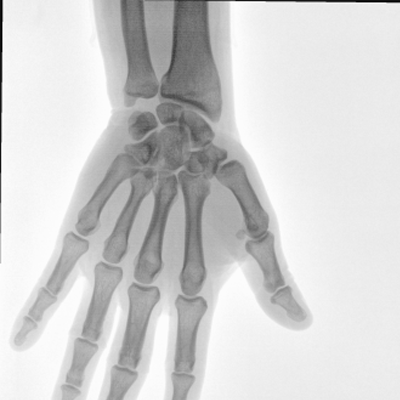

大尺寸動態(tài)平板探測器,高DQE、低噪聲、圖像清晰。采用多分辨率圖像增強(qiáng)處理技術(shù),不同部位不同圖像處理算法,滿足客戶多樣化的需求。

采用智能變頻脈沖透視技術(shù),優(yōu)化圖像質(zhì)量的同時降低輻射劑量,呵護(hù)醫(yī)患健康